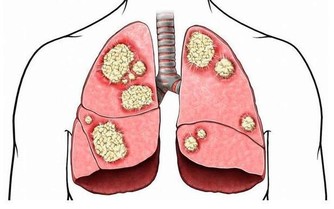

膝蓋關節一直是諸多長輩的困擾 尤其到了中老年又缺乏運動的情況下 很容易伴隨著天氣或者其他原因而不適 可是沒想到這些問題讓一顆便宜隨處可見的洋蔥改善了! 做法: 材料:洋蔥2個,紅葡萄酒500毫升,1瓶普通紅葡萄酒配三個洋蔥。 製法:將洋蔥洗凈,去掉表麵茶色外皮,切成八等份約半月形 將洋蔥洗凈,去掉表將洋蔥裝入玻璃瓶內,加入紅葡萄酒,(將剝下來的外皮也一起加入效果更好 將玻璃瓶蓋好密封,在陰涼地方放置約2至8日。(筆者覺得一星期最好) 將玻璃瓶的洋蔥片,用濾網過濾後,洋蔥、酒分開裝入瓶中,放置在冰箱中冷藏 飲用方法: 一. 每日約一杯(50毫升),年紀大的人每次20毫升左右; 二. 每日飲一至兩次; 三. 浸過酒的洋蔥片一起食用更好; 四. 不喝酒的人,可用兩倍左右的開水稀釋後飲用或每次倒入電鍋內煮約4至5分鐘,蒸發酒精後飲用。 洋蔥治療膝蓋疼效果驚人 看到這裡大家是否覺得很容易呢?究竟又可以治那些病呢? 讓筆者告訴大家,其功效對膝蓋! 疼痛、白內障、老人痴呆的效果相當驚人,日本非常流行。 一. 高血壓的患者,飲了之後血壓正常且安定,也會降低糖尿值,把血糖下降。 二. 每晚都要去幾次廁所的夜晚頻尿症,喝了兩天之後,不可思議的完全恢復正常。 三. 每天夜裡醒來,一直到天亮都不能再入睡的,不食安眠藥不能入睡的不眠症,飲用之後也會全消除。 四. 經常肚子會脹,非常痛苦的便秘症,喝了之後第二天便恢復正常排便。 吃洋蔥的好處 補充:討厭吃洋蔥嗎?看看下面的文章,即使它再不可口,為了身體好,也請多多食用。 【洋蔥比骨質酥鬆症的藥有效】 權威期刊「自然」的最新研究報告指出,洋蔥是最能夠防止骨質流失的一種蔬菜。洋蔥預防骨質流失的效果,甚至比骨質酥鬆症治療藥品還要好。 【洋蔥可以預防膽固醇過高】 據哈佛醫學院心臟科教授克多格爾威治博士指出,每天生吃半個洋蔥,或喝等量的洋蔥汁,平均可增加心臟病人約30%的HDL含量(HDL為高密度脂蛋白膽固醇,一種被認為有助於預防動脈粥狀硬化的膽固醇,也是一種的好的膽固醇。) 【洋蔥可以分解脂肪】 克多博士讓診所里的心臟病人每天吃洋蔥,結果發現洋蔥里所含的化合物也能阻止血小板凝結,並加速血液凝塊溶解。所以,當你享用高脂肪食物時,最好能搭配些許洋蔥,將有助於抵銷高脂肪食物引起的血液凝塊;所以說牛排通常搭配洋蔥一起吃,是很有道理的。 【洋蔥可以對抗哮喘】 洋蔥含有至少三種抗發炎的天然化學物質,可以治療哮喘。由於洋蔥可以抑制組織胺的活動,而組織胺正是一種會引起哮喘過敏症狀的化學物質;據德國的研究,洋蔥可以使哮喘的發作機率降。 【洋蔥可以治療糖尿病】 很久以前,洋蔥就被用來治療糖尿病,到了現代,醫學也證明洋蔥確實能夠降血糖;而且不論生食或熟食,都同樣有效果。原來洋蔥里有一種抗糖尿病的化合物,類似常用的口服降血糖劑甲磺丁胺,具有刺激胰島素合成及釋放的作用。